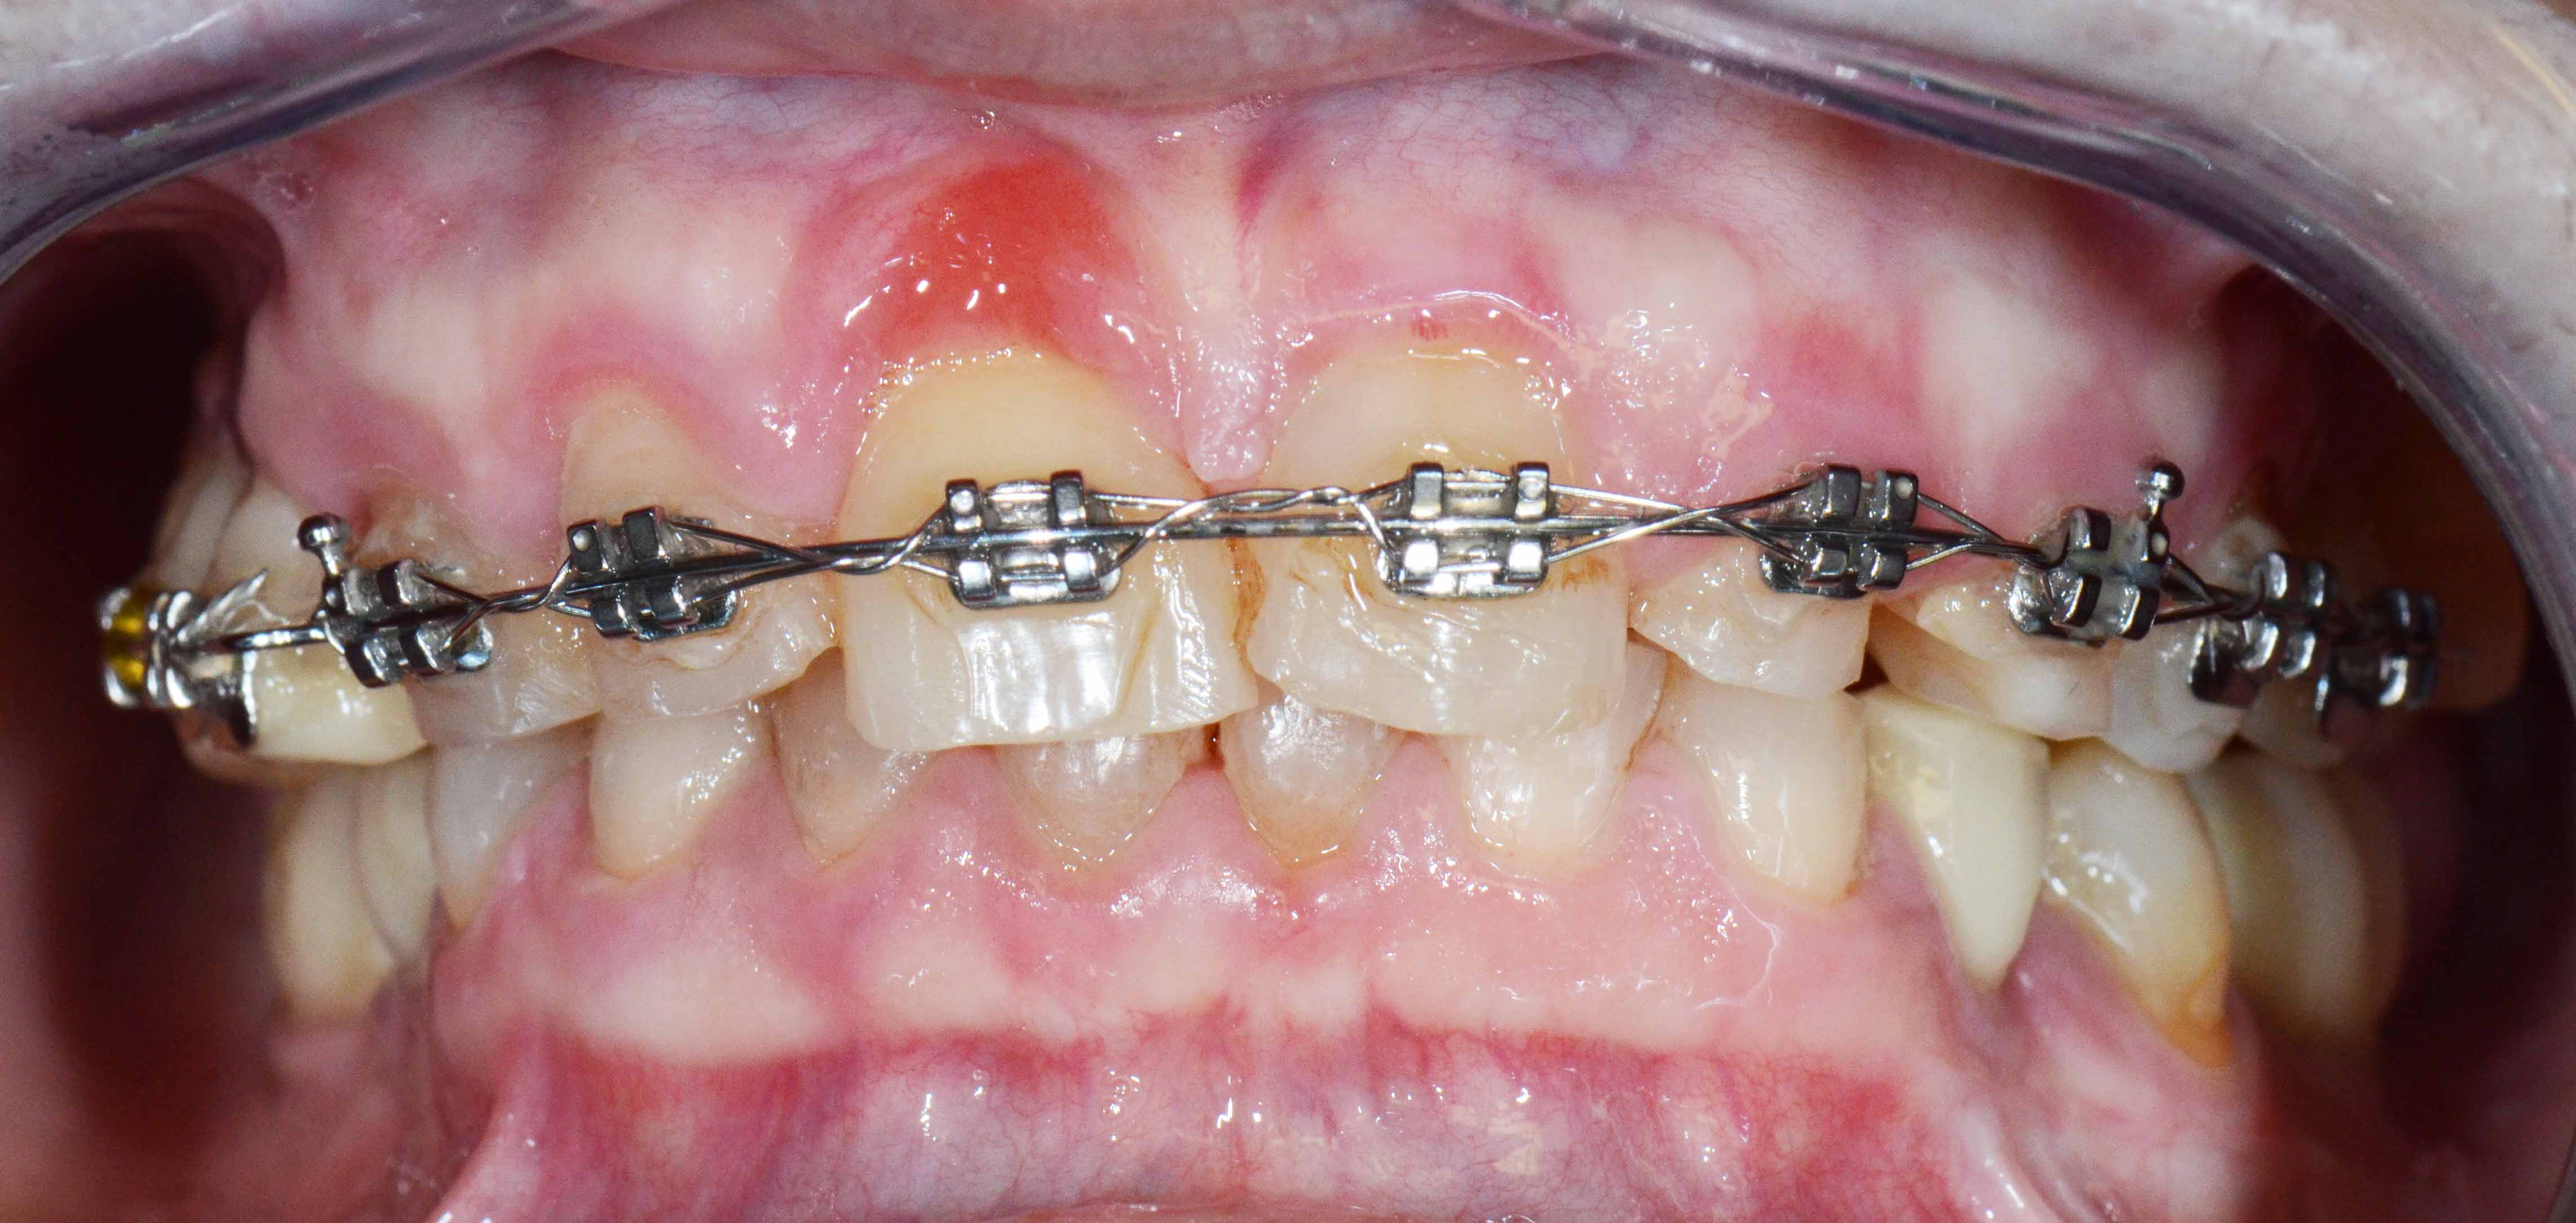

Mantiveram-se os dentes naturais remanescentes que tinham bom prognóstico e com Aparelho Ortodôntico fixo foram corrigidas as suas posições.

Alterações de Cor por Tetraciclinas

Alterações de cor devido a utilização de Tetraciclinas em criança. Vários tratamentos feitos ao longa da vida para disfarçar o problema sem resultados satisfatórios.